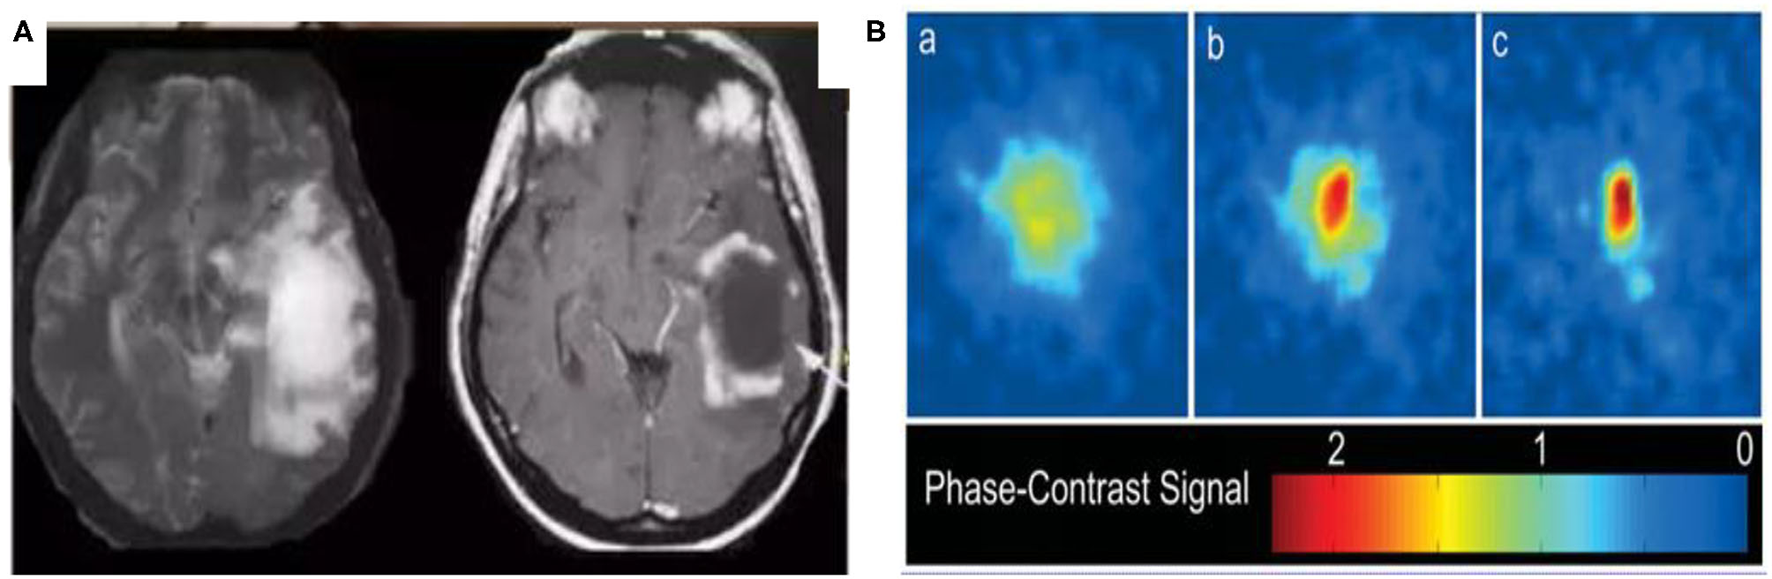

In the following section, we investigate the similarities between glioma and the BEC through the analysis of their shape. Figure 2A is a typical image of glioma1 and Figure 2B is a 2D image of a BEC2. We can immediately see that the shape of the glioma is similar in appearance to that of the BEC. For example, all atoms tend to stick together when a BEC of a million atoms is achieved under a shallow temperature. When a one million atom BECs at the lowest temperature, all atoms tend to stick together. According to the formula of quantum mechanics, the shape of BEC condensation process can be expressed by an equation. Similarly, due to irritant factors, if brain cells cannot balance growth and division, a glioma may develop into a shape similar to that of the BEC. Therefore, we predict and assume that the glioma shape might have the same quantum mechanics formulation as that of the BEC.

Figure 2

Similarities between glioma and BEC. (A) glioma of T2W1, (B) 2D image of BEC. a: before the appearance of a BEC. b: just after the appearance of the condensate. c: nearly pure condensate.

Figure 2 highlights similar properties in the shape of Bose-Einstein Condensate (BEC) and glioma.